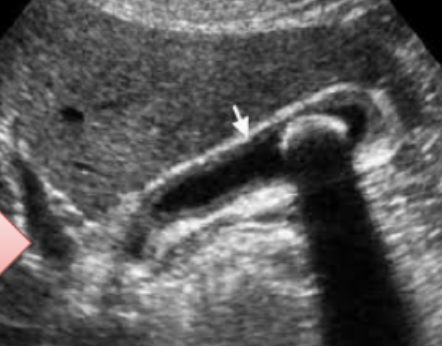

U/S from patient with recurrent upper abdominal pain.

Diagnosis -

calculous cholecystitis

Four common complications

- cholangitis

- peritonitis

- perforation

- choledocholithiasis

An ultrasound image from a patient with recurrent upper abdominal pain.

Q1: What is your diagnosis?

- Cholecystitis

Q2: Name FOUR common complications of this disease.

- Cholangitis,

- Peritonitis,

- Perforation,